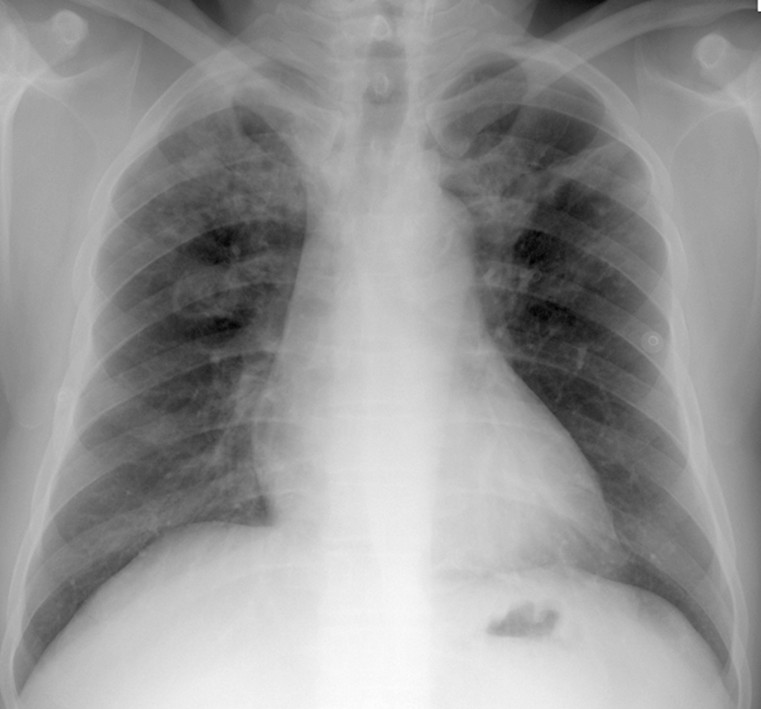

病例1:重症肺炎

男性,85岁,发热、气短。1月17号表现为两肺斑片状实变影,经过一轮治疗,效果欠佳,病情继续进展,两肺比较对称,没有心衰,也没有水肿的改变。最终诊断是重症肺炎,调整碳青霉烯类药物的治疗后有所好转。